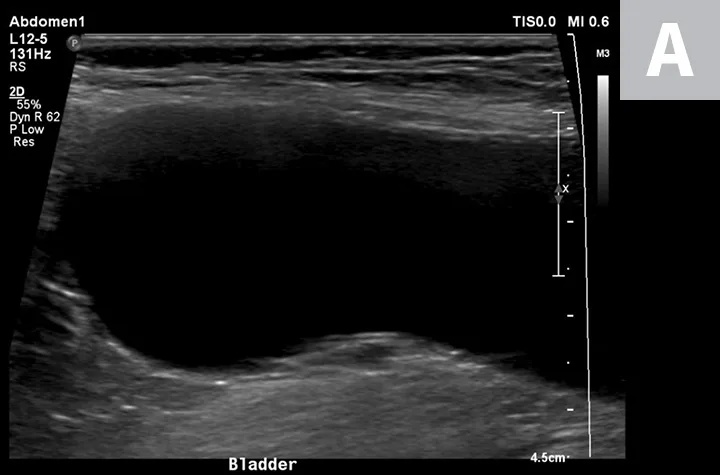

FIGURE 1

Ultrasonographic image showing the cranial aspect of the urinary bladder (A), identified just before ultrasound-guided cystocentesis. It is important to adjust the depth of the image so that the urinary bladder is focused and to consider the depth of the urinary bladder using a machine scale that should be present on the ultrasound screen; in smaller patients the needle may only be partially inserted and not reach the hub (B; arrow).